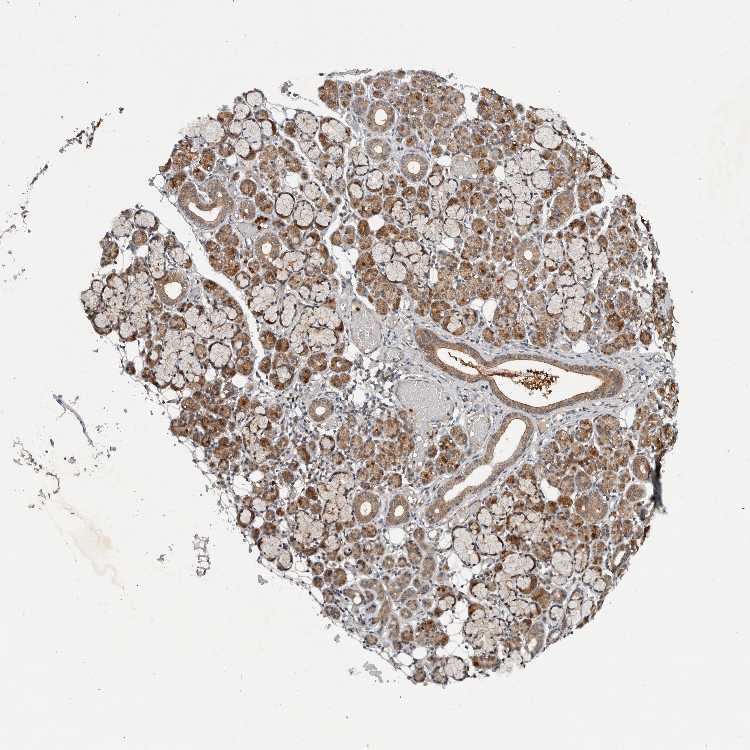

SALIVARY GLAND - Antibody stainingi

Antibody staining in the annotated cell types in the current human tissue is reported as not detected, low, medium, or high, based on conventional immunohistochemistry profiling in selected tissues. This score is based on the combination of the staining intensity and fraction of stained cells.

Each image is clickable and will lead to virtual microscopy that enables deeper exploration of all samples and also displays staining intensity scores, fraction scores and subcellular localization as well as patient and tissue information for each sample.

Antibody HPA026713

Glandular cells Medium